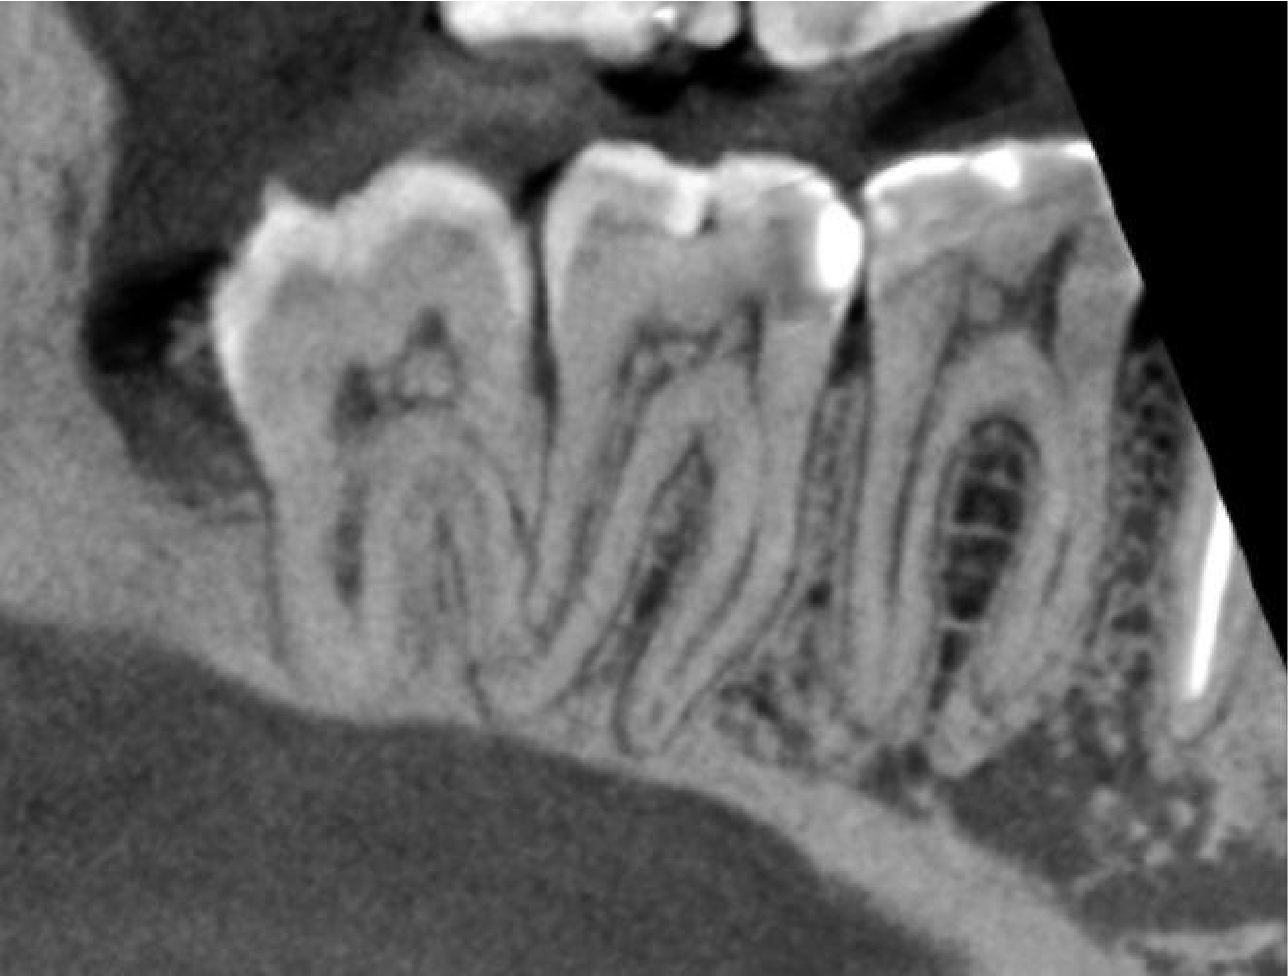

The LR6 has patent root canals, normal periodontal ligament width and lamina dura. The most likely explanation for the pain is a non-vital pulp and/or a root fracture. No root fracture is visible.

Cropped panoramic of LR6-8 and cross section of alveolar ridge of LR6 region showing patent root canals, normal periodontal ligament width and lamina dura. Also seen is the enlarged follicle space associated with the LR8.